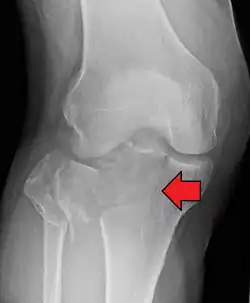

| A severe tibial plateau fracture with an associated fibular head fracture | |

A tibial plateau fracture is a break of the upper part of the tibia (shinbone) that involves the knee joint.[1] This could involve the medial, lateral, central, or bicondylar (medial and lateral).[3] Symptoms include pain, swelling, and a decreased ability to move the knee.[1] People are generally unable to walk.[2] Complication may include injury to the artery or nerve, arthritis, and compartment syndrome.[1]

In all injuries to the tibial plateau radiographs (commonly called x-rays) are imperative. Computed tomography scans are not always necessary but are sometimes critical for evaluating degree of fracture and determining a treatment plan that would not be possible with plain radiographs.[10] Magnetic Resonance images are the diagnostic modality of choice when meniscal, ligamentous and soft tissue injuries are suspected.[11][12] CT angiography should be considered if there is alteration of the distal pulses or concern about arterial injury.

A tibial plateau fracture seen on X-ray